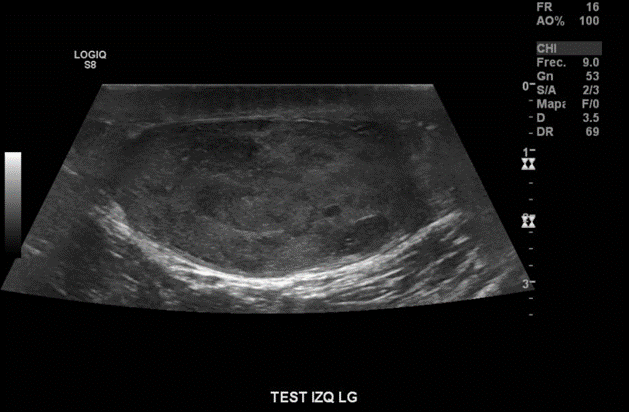

Descripción de hallazgos:

Testículo izquierdo heterogéneo, con áreas hipoecogénicas, tenue señal al Doppler, con imagen nodular hipoecogénica, heterogénea, con señal al Doppler, sugerente de neoplasia